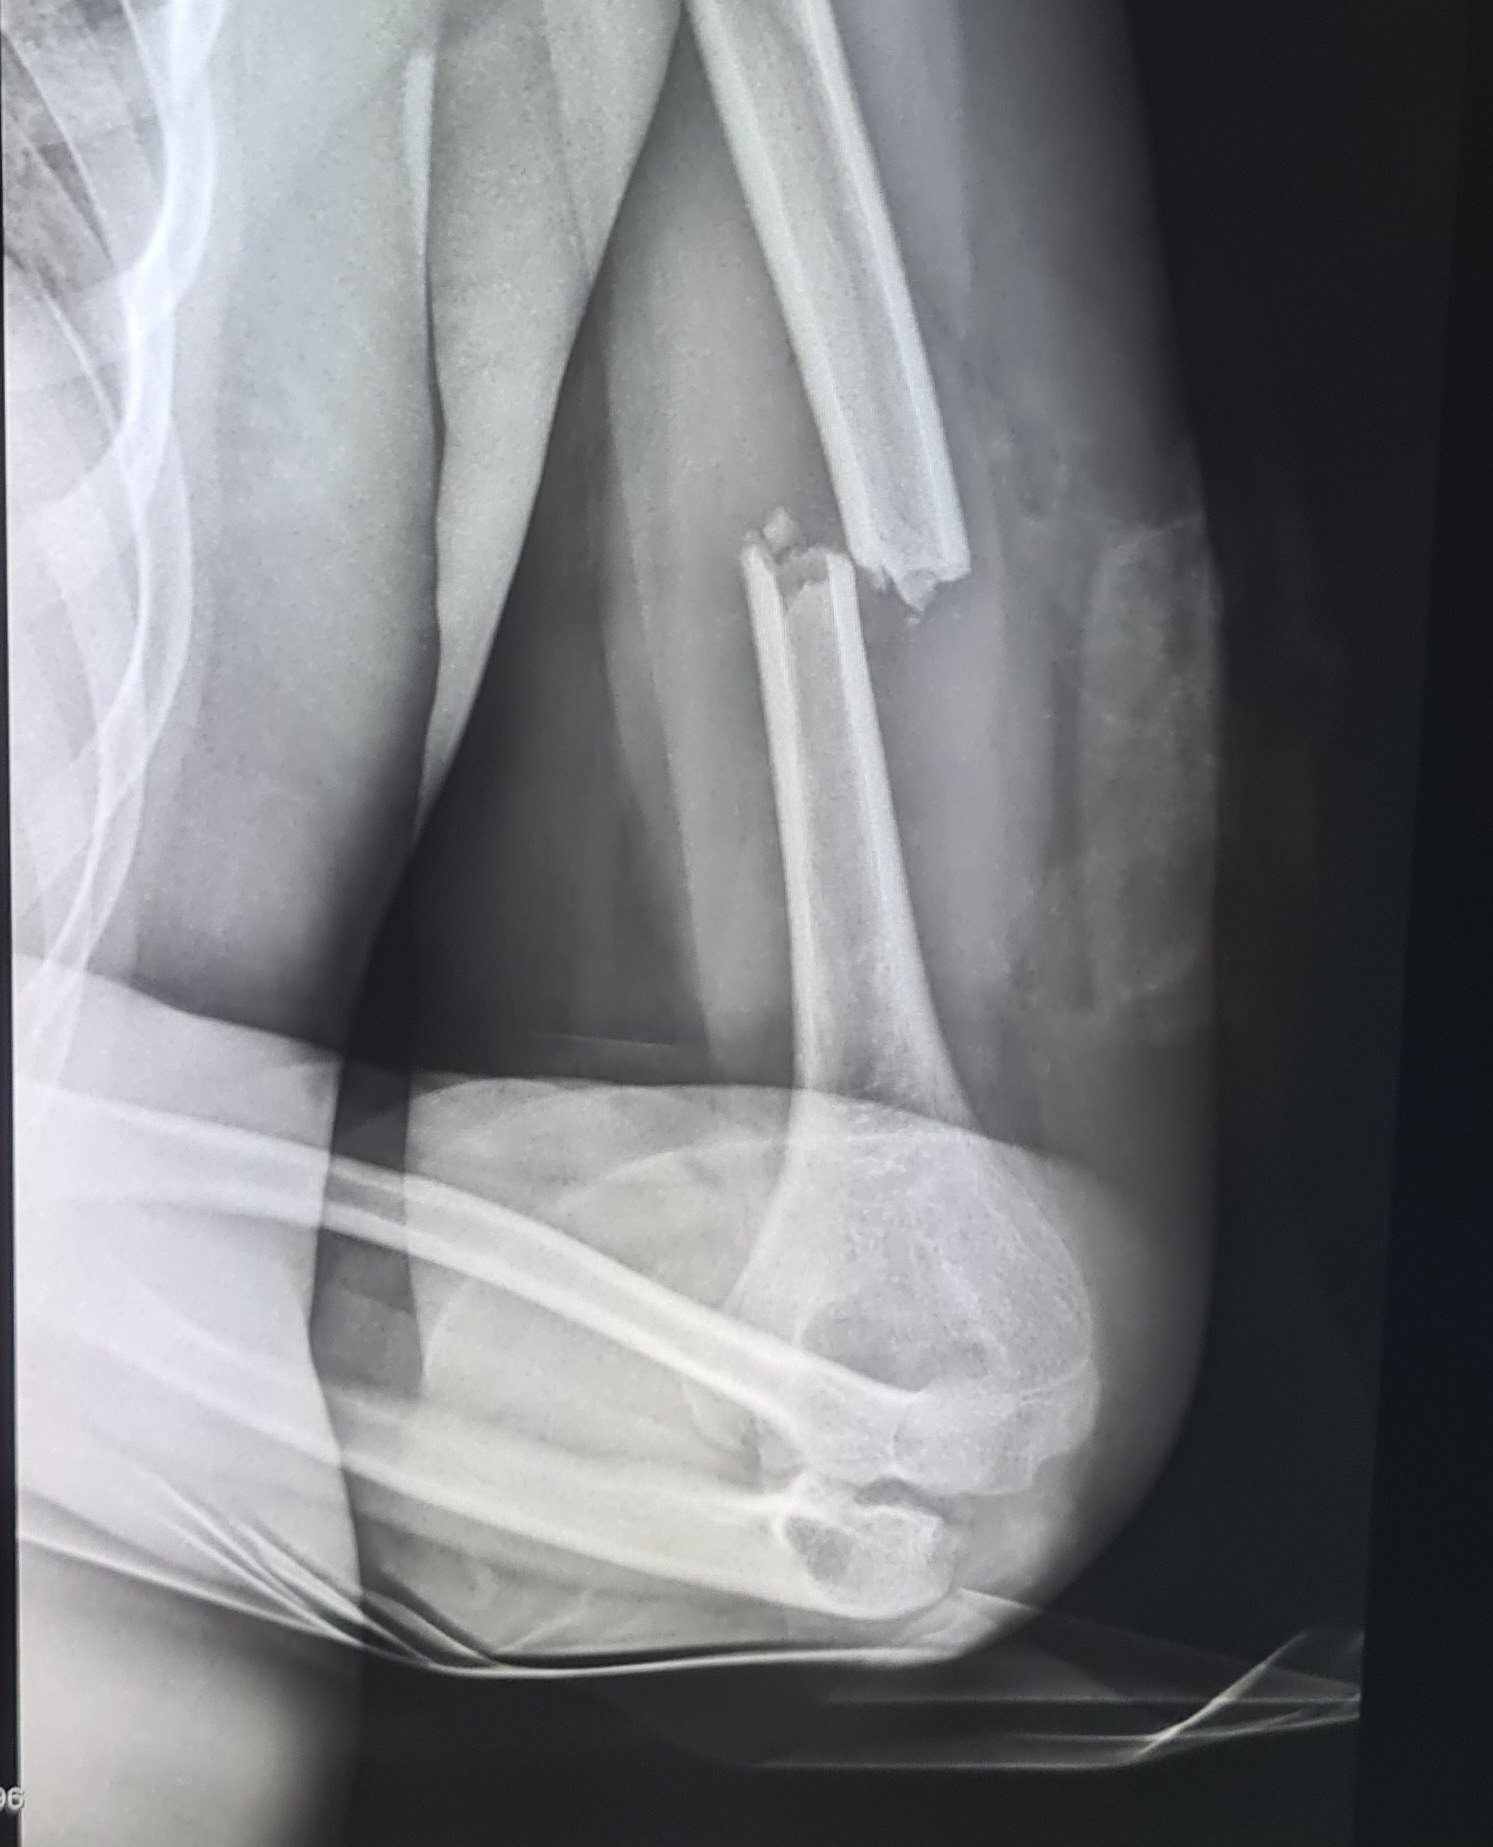

A mentők a Bethesda Gyermekkórházba vitték, ahol nyílt felkartörést diagnosztizáltak nála. A fiút a sebészeti osztályon látták el, majd műtétre volt szükség. A kórház hangsúlyozza: az ilyen esetek egyáltalán nem ritkák, és az orvosok rendszeresen találkoznak hasonló balesetekkel.